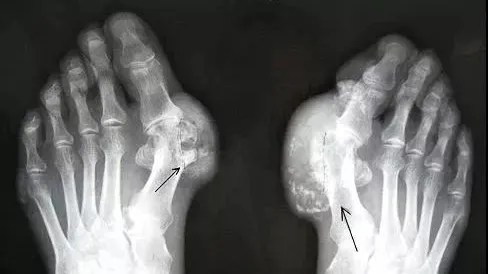

痛风石是指在痛风患者发病过程中,出现的一种坚硬的像石头一样的结节,是由体内的尿酸形成的结晶。它们会破坏关节和骨骼,导致关节畸形、活动障碍,甚至破溃流脓、难以愈合。

长期未控制,尿酸盐结晶在关节软骨、滑膜、肌腱、皮下甚至耳廓等处大量沉积,形成大小不一的黄白色结节。一般患者自己可观察到或触摸到皮下有凸起,伴或不伴发红,或者有包块,或能感受到疼痛、发热,甚至感觉关节活动受到影响,在医学上称为“痛风石”。

痛风石一般好发的部位主要有,耳廓、眼睑、关节部位的皮下,典型部位在耳廓,也常见于足趾、手指、腕、踝、肘等关节周围。